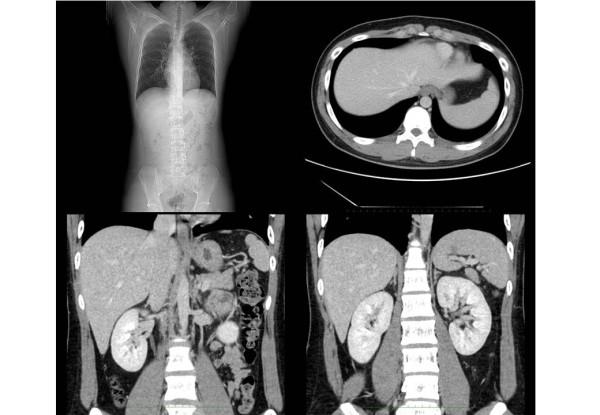

We present a 17-year-old Japanese boy with left-upper-quadrant pain for two months. Chest radiography showed an elevated left hemidiaphragm. Computed tomography revealed a congenital diaphragmatic hernia. The spleen and left colon had been displaced into the left thoracic cavity through a left posterior diaphragmatic defect. We diagnosed a Bochdalek hernia. Surgical treatment was performed via a thoracoscopic approach. The boy was placed in the reverse Trendelenburg position and intrathoracic pressure was increased by CO2 gas insufflations. This is a very useful procedure for reducing herniated contents and we were able to place the herniated organs safely back in the peritoneal cavity. The diaphragmatic defect was too large to close with thoracoscopic surgery alone. Small incision thoracotomy was required and primary closure was performed. His postoperative course was uneventful and there has been no recurrence of the diaphragmatic hernia to date.

我们报告一名17岁的日本男孩,左上腹疼痛两个月。胸部X线片显示左半膈肌抬高。计算机断层扫描显示先天性膈疝。脾脏和左结肠通过左后膈肌缺损移入左胸腔。我们诊断为波氏孔疝。通过胸腔镜手术进行治疗。男孩置于头低脚高位,通过二氧化碳气体注入增加胸腔内压力。这是一种非常有用的减少疝内容物的方法,我们能够将疝出的器官安全地放回腹腔。膈肌缺损太大,仅通过胸腔镜手术无法闭合。需要小切口开胸并进行一期缝合。他术后恢复顺利,迄今为止膈疝未复发。